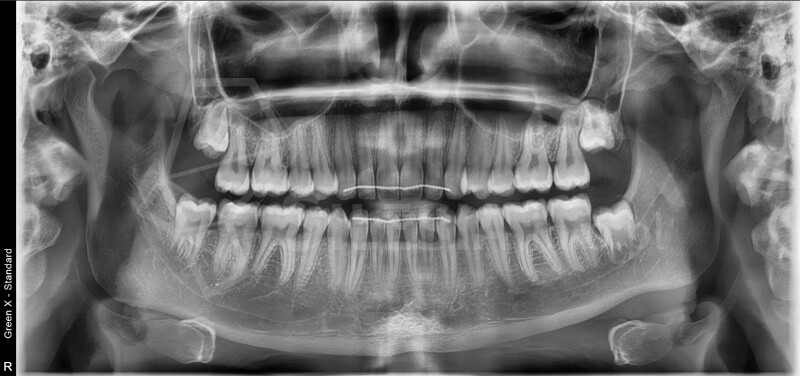

Pracownia wyposażona jest w tomograf stożkowy Vatech Green X (model 2025) – najnowszej generacji urządzenie, które łączy najwyższą jakość obrazów 2D i 3D z minimalną dawkąpromieniowania.

Zdjęcie panoramiczne (pantomogram) obejmuje całe uzębienie i szczęki, pokazując zmiany, których nie widać na zdjęciach punktowych RTG – takie jak torbiele, guzy, stany zapalne czy zwyrodnienia stawów.

CBCT (tomografia stożkowa) to nowoczesne badanie 3D, które pokazuje zęby, kości, zatoki i stawy skroniowo-żuchwowe w pełnym trójwymiarze. Umożliwia bardzo dokładne zaplanowanie leczenia chirurgicznego, ortodontycznego, implantologicznego i laryngologicznego.